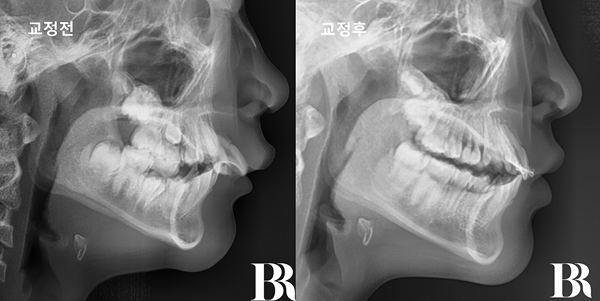

나이 : 12세

성별 : 남자

내원 이유 : 윗니가 뻗어 있다

치료방법 : 턱교정(1차교정) 엑티베이터 with 헤드기어

치료시작 : 2024년 7월

치료종료 : 2025년 11월

치료기간 : 1년 4개월

1년 4개월 간 이루어진

턱교정치료가 끝났습니다.

아래턱이 이쁘게 나왔고

윗니와 아랫니의 앞뒤 차이가

정상 범위 내로 줄어들었습니다.

발치교정을 요하지 않는

상태로 만들었습니다^^